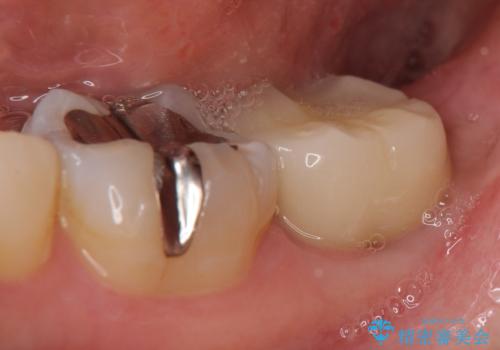

- 左下奥歯でものを咬むと鈍い痛みがあるので診て欲しいといらっしゃった方の症例です。

検査の結果根尖病変(歯根の細菌感染)を認めたため、再根管治療を行いオールセラミッククラウンによる補綴を行いました。